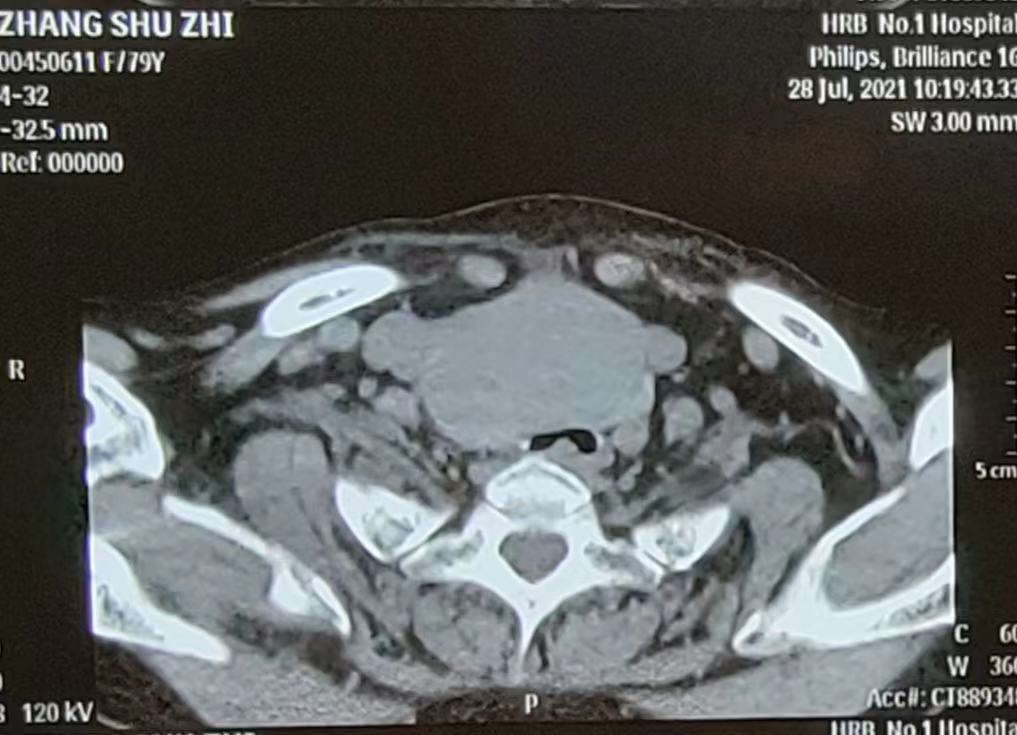

80歲的張大娘是由120救護車轉運到市一院急診科的重症患者,來時頸部明顯腫大並伴有呼吸困難,命懸一線。普外四科(甲狀腺外科)主任齊明及耳鼻喉科主任王瑋迅速趕去緊急會診並與急診科一道積極搶救患者。仔細詢問家屬後得知,80歲的張大娘之前就患有甲狀腺結節,但由於年事較高且伴有其他基礎疾病,一直未能系統治療。三天前,張大娘「感冒」後伴隨劇烈的咳嗽咳痰,隨後頸前的甲狀腺明顯增大並伴有呼吸困難的情況。CT上可見巨大的甲狀腺腫物直徑達8cm,氣管被壓扁,最窄的位置僅剩餘5毫米左右。這兩日,家屬陪伴張大娘輾轉就診於省內多家大醫院,卻因為風險太高而沒有醫生願意為其手術。